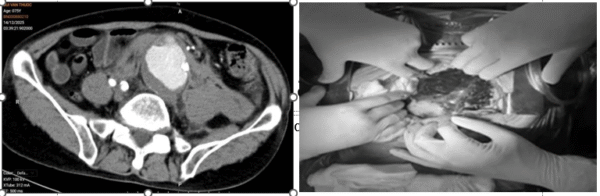

Hình ảnh khối máu tụ do vỡ động mạch chủ bụng trên phim chụp CLVT và sau khi mở bụng - Ảnh BVCC

Người bệnh nam, 75 tuổi, nhập viện lúc nửa đêm trong tình trạng đau bụng dữ dội, huyết động không ổn định. Qua thăm khám lâm sàng và hình ảnh chụp cắt lớp vi tính (CLVT), các bác sĩ xác định người bệnh bị vỡ phình động mạch chủ bụng kèm khối máu tụ lớn trong ổ bụng, đe dọa trực tiếp đến tính mạng.

Ngay lập tức, bệnh viện kích hoạt hệ thống báo động đỏ, khởi động quy trình cấp cứu và phối hợp đa chuyên khoa: cấp cứu, chẩn đoán hình ảnh, gây mê hồi sức, phẫu thuật tim mạch – lồng ngực và hồi sức tích cực – chống độc yêu cầu.

Với tinh thần khẩn trương, quyết liệt cùng năng lực chuyên môn vững vàng, kinh nghiệm dày dạn, ê-kíp đã nhanh chóng thực hiện phẫu thuật và kiểm soát chảy máu, ổn định huyết động; thay đoạn động mạch chủ, đưa người bệnh trở về từ “lằn ranh sinh tử”.